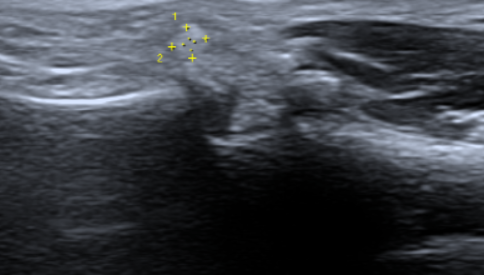

엄지손가락이랑 손바닥 이어지는 사이에 혹같은게 생겼습니다 크기는 크지않은데 움직일때 아프도라고요 1차병원에서는 상급병원으로 가라고 해서 3차 병원 성형외과 수부쪽으로 다녀왔는데 크기로는 결절종인것같다고 근데 초음파를 정확하게 찍어봐야안다 자긴 잘 모른다면서(판독지 없었음) 초음파를 한번 더 찍으라네요 결절종이면 3차 아니어도 1차나 2차병원에서 일단은 주사로도 해결 가능한 부분이니 다시 2차병원으로 갈 예정인데 보기엔 어때보이시나요?

• 2번 째 사진